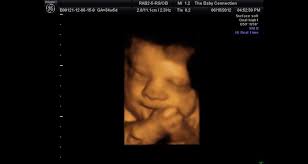

Baby connection roseville hours. The Baby Connection 4d 3d Hdlive Ultrasound Roseville. Im shocked it hasnt been reviewed before. You can feel confident in knowing that your ultrasound session will be provided by trained.

246 customer reviews of The Baby Connection. Up to 30 printable images emailed directly to you upon request. Contact us or Book Online for an appointment today.

3101 likes 6 talking about this 5666 were here. A unique 3D4D fetal ultrasound company offering Hd Live now. Ladies if you are looking for an affordable 3d4d ultrasound The Baby Connection is the place to go. The Baby Connection allows you to see what your baby looks like before they are born by the use of our state-of-the-art 3D4D and HDlive fetal ultrasound. 267 reviews of The Baby Connection I cant believe that I had to add this business to Yelp. 20 avaliações detalhes de contato e horário de funcionamento para The Baby Connection em 1211 Pleasant Grove Blvd Ste 100 Roseville CA. I started looking for an ultrasound place once my hubby and I found out he would be leaving for 2 12 months to Basic Training for the Air Force. The Baby Connection Inc. 246 customer reviews of The Baby Connection.

The Baby Connection Roseville CA. If you are looking for baby connection roseville hours simply check out our links below. Gender determination upon request. I started looking for an ultrasound place once my hubby and I found out he would be leaving for 2 12 months to Basic Training for the Air Force. A unique 3D4D fetal ultrasound company offering Hd Live now. The Baby Connections is a unique keepsake fetal ultrasound company that provides a mobile service as well as office visitsOur mobile service is the only service of its kind in our areaWe are located in Roseville California and we service Sacramento Placer and Sutter countyWe make all this possible for you by bringing you the Voluson i which is a portable. The receptionists both times were super friendly and455251.